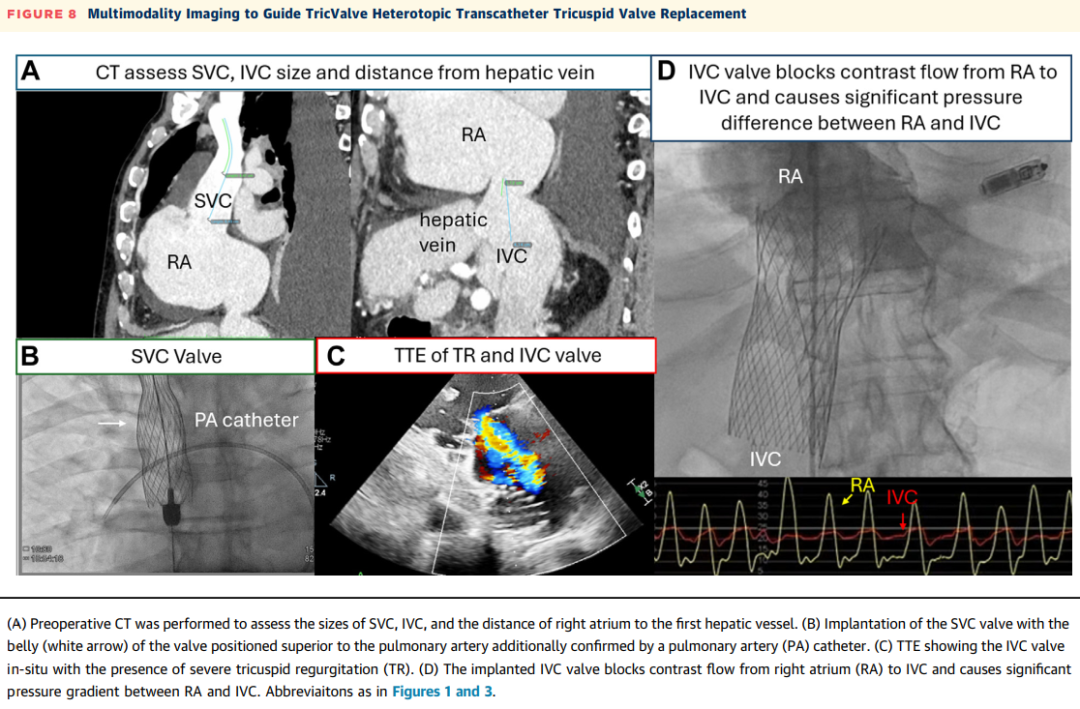

腔静脉瓣植入术已被用于有常规经导管介入治疗解剖学禁忌证的患者,以保护器官免受静脉高压,并减少TR。TricValve(P&F Products & Features)是一种通过股静脉通路输送的异位双瓣腔静脉瓣(见图8,视频3)。TRICUS/TRICUS EURO研究的综合分析纳入了44例严重症状性TR患者。在TricValve植入术后1年的随访中,95.5%(44例中的42例)的患者KCCQ评分从基线增加≥15分、NYHA心功能分级改善至I级或II级,或6分钟步行测试距离增加≥40米。接受TricValve植入术的患者在6个月随访CT中,右心室中部直径从48.6±9.9毫米减少至43.0±7.3毫米(P=0.001)。TricValve具有两个专用的自膨胀镍钛合金支架和牛心包瓣叶,分别植入下腔静脉和上腔静脉,以消除系统性静脉淤血。植入术可以在纯透视引导下进行,也可以辅以经胸超声心动图和TEE引导。

图8 多模态成像引导TricValve异位TTVR术